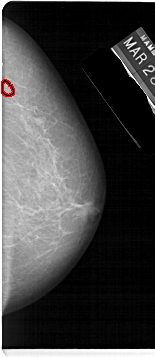

A_1579_1.LEFT_MLO

LEFT_MLO LINES 5491 PIXELS_PER_LINE 2641 BITS_PER_PIXEL 12 RESOLUTION 43.5 NON_OVERLAY

FILE: A_1579_1.RIGHT_MLO.OVERLAY

TOTAL_ABNORMALITIES 1

ABNORMALITY 1

LESION_TYPE MASS SHAPE IRREGULAR MARGINS ILL_DEFINED

ASSESSMENT 4

SUBTLETY 1

PATHOLOGY MALIGNANT

TOTAL_OUTLINES 1

BOUNDARY